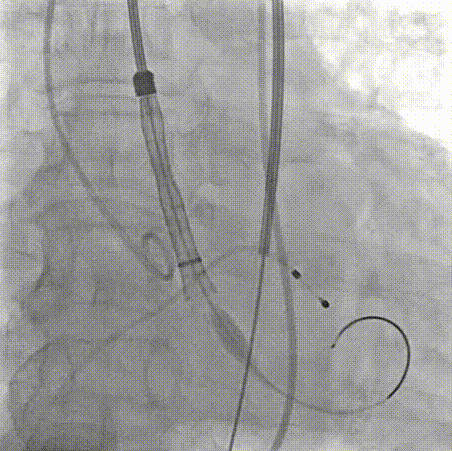

交换猪尾导管测压

瓣膜位置形态良好

术后压差从45 mmHg降至2mmHg

超声显示瓣膜形态良好,血流动力学优异